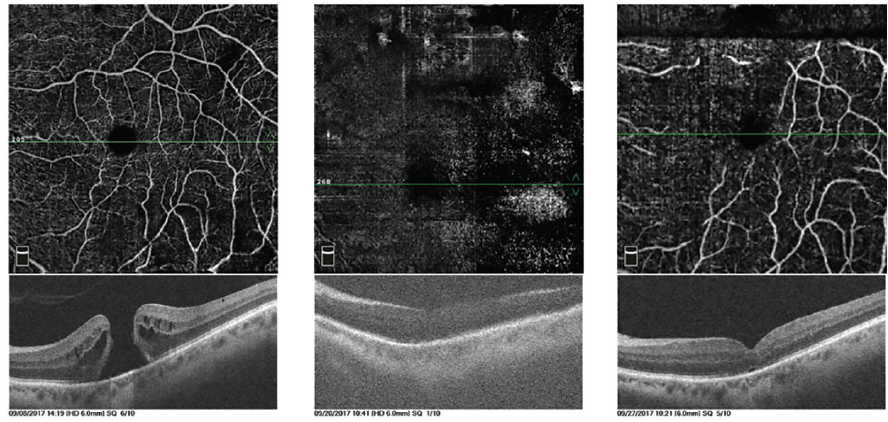

<p>Figure 1. Superficial en face OCTA images of a 74-year-old pseudophakic woman before surgery (left column), at postoperative day 1 (middle column), and at postoperative week 1 (right column). The OCTA scan followed the course of the retinal vessels, localized the fovea, and obtained the best quality images with gas in place. Although resolution was limited in the postoperative day 1 image, MH closure was evident, and FDP was discontinued. BCVA improved from 20/200 before surgery to 20/40 at 6 months.</p>

Figure 1. Superficial en face OCTA images of a 74-year-old pseudophakic woman before surgery (left column), at postoperative day 1 (middle column), and at postoperative week 1 (right column). The OCTA scan followed the course of the retinal vessels, localized the fovea, and obtained the best quality images with gas in place. Although resolution was limited in the postoperative day 1 image, MH closure was evident, and FDP was discontinued. BCVA improved from 20/200 before surgery to 20/40 at 6 months.